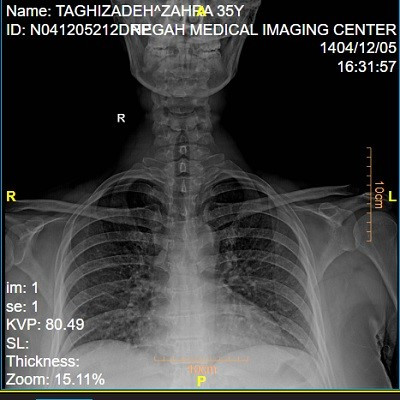

تشخیص تیروئیدیت بر اساس شرح حال ، معاینه فیزیکی و آزمایش های خونی انجام می شود. اندازه گیری هورمون های T3 ،T4  ،TSH به همراه بررسی آنتی بادی های تیروئیدی در شناسایی نوع بیماری کمک می کند. در برخی موارد سونوگرافی تیروئید یا اسکن رادیونوکلئید برای ارزیابی ساختار و عملکرد غده انجام می شود.